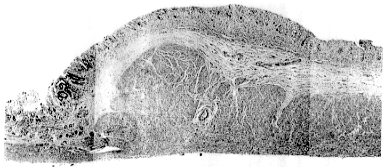

Although the nature and function of the pyloric ring is often debated, few deliberate attempts have been made to determine its microscopic anatomy. Consequently sections of the ring were done more than 6 hours post-mortem in 7 subjects varying in age from 9 months to 83 years, who had succumbed to non-gastrointestinal causes; a total of 20 sections were examined (Table 11.2). In all cases the pyloric ring is seen to consist of muscular and mucosal/submucosal components (Fig 11.3). For instance, in a 9 month old subject the muscular component is seen to be 2.0mm in height, and the overlying mucosal component 1.0mm. In a 5 year old subject the approximate figures are 5.5mm and 1.5mm respectively, and in a 44 year old subject 5.5mm and 1.5mm respectively.

![]() |

| Fig. 11.3. Microscopic section of normal pyloric ring. The muscular component measures 4.5 mm, the mucosal/submucosal component 1.5 mm in height |